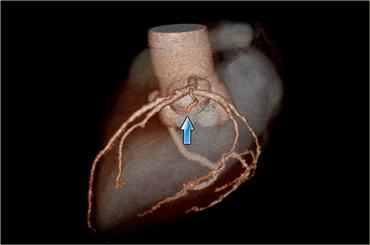

LAD đi trong rãnh liên thất trước và kéo dài đến tận mỏm tim.

LAD cấp máu cho phần trước của vách liên thất qua các nhánh vách và thành trước thất trái qua các nhánh chéo.

LAD cấp máu cho phần lớn thất trái và cả bó nhĩ thất.

Gợi nhớ: Các nhánh Chéo xuất phát từ LAD (nhánh Diagonal từ LAD).

Các nhánh chéo tách ra từ LAD và chạy sang bên để cấp máu cho thành trước bên của thất trái.

Nhánh chéo đầu tiên đóng vai trò là ranh giới giữa đoạn gần và đoạn giữa của LAD (2).

Có thể có một hoặc nhiều nhánh chéo: D1, D2, v.v.